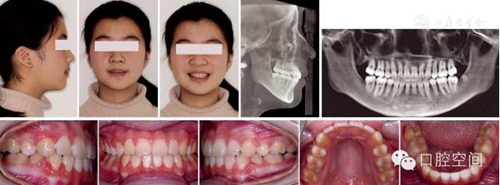

女性,11歲,表現(xiàn)為骨型Ⅱ類錯頜畸形,高角,下頜后縮,上下牙弓前突。X線片顯示正處于生長發(fā)育高峰期。治療前面頜像及X線片見圖2。通過拔除4個第一前磨牙,應用標準方絲弓定向力技術矯治,并在上頜第一磨牙近中植入種植體。初始弓絲上頜為0.017×0.022英寸不銹鋼方絲(1英寸=2.54 cm),下頜為0.018×0.025英寸不銹鋼方絲,佩戴高位J鉤牽引頭帽12小時/天,先牽引尖牙往遠中,再換用0.020×0.028英寸和0.019×0.025英寸不銹鋼方絲分別彎制關閉曲內收上下切牙關閉間隙,在內收前牙的同時,對上頜后牙進行垂直向的主動壓低。間隙關閉后應用10-2支抗預備系統(tǒng)直立下頜后牙,上頜始終通過高位J鉤牽引頭帽進行垂直向控制。最后下頜換用0.0215×0.028英寸全尺寸弓絲穩(wěn)定下牙列,使用Ⅱ類牽引和垂直牽引,對Ⅱ類關系進行過矯正。治療中面頜像見圖3。通過25個月的矯治,拆除矯治器,制作佩戴保持器。治療后FMA減少了1°,F(xiàn)MIA和Z角均接近正常值(表3),下頜骨垂直向生長明顯,治療后面型明顯改善,咬合關系良好。治療后面頜像及X線片見圖4,治療前后頭影測量對比圖見圖5。

圖2典型病例治療前面像及X線片